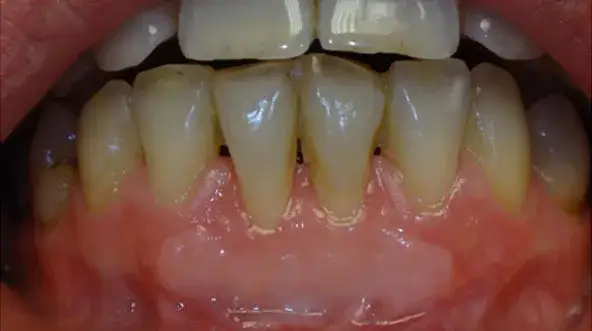

Podrażnione dziąsła? Odkryj domowe sposoby na szybką ulgę, skuteczne leki z apteki i dowiedz się, kiedy iść do dentysty. Sprawdź nasz poradnik!